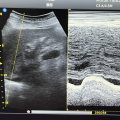

术后CT

最近一次头胸CT